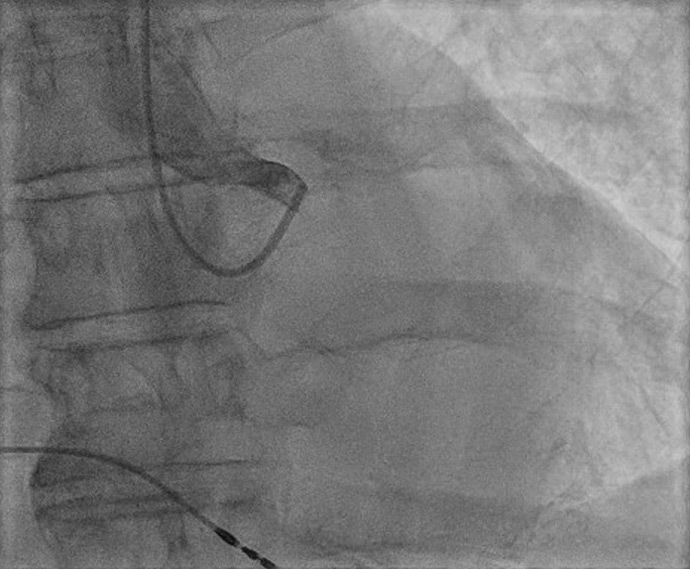

Unravelling a puzzle